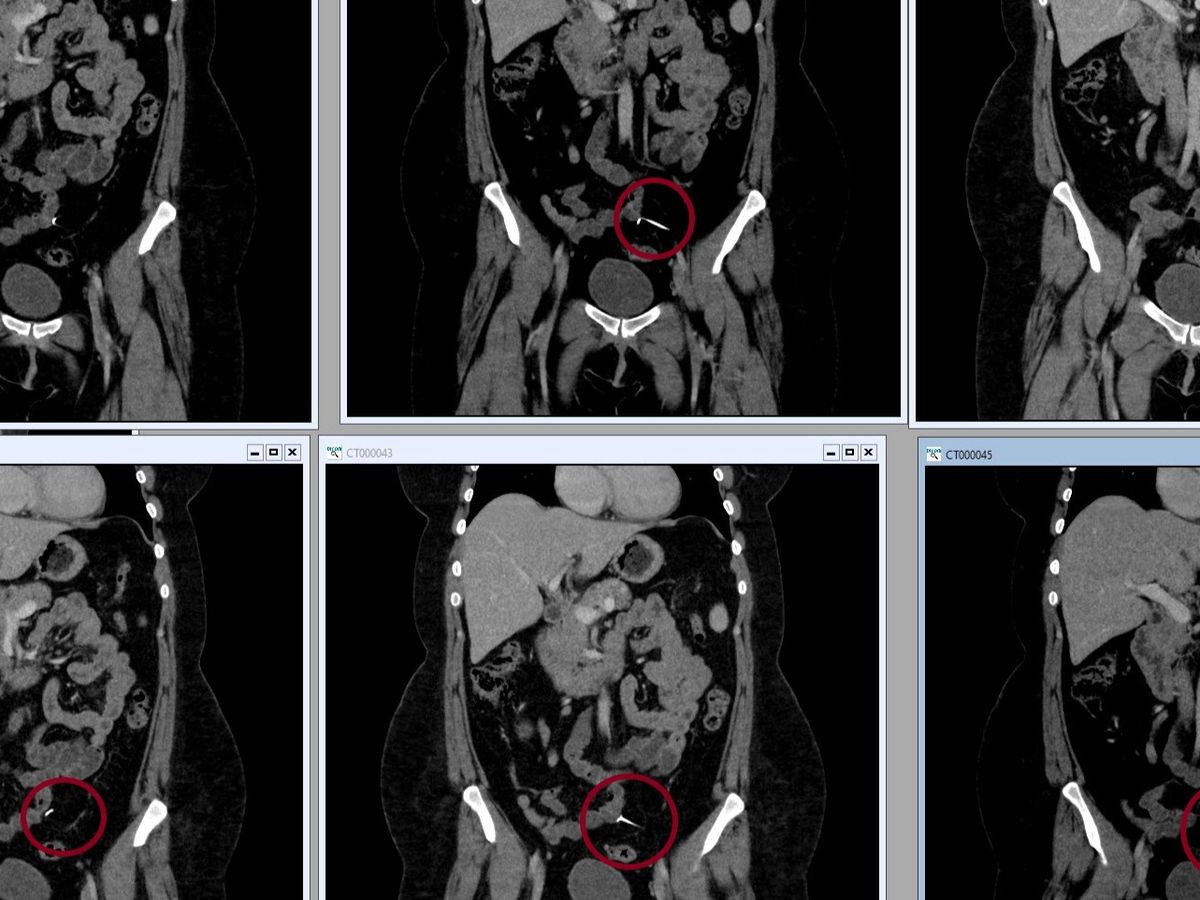

CT scan proof added to the bottom of this explanation.

My actual CT scan results pic:

- June 29th 2024 I saw my primary doctor complaining of sharp pelvic pain. The same pain I have right now. This doctor saw that October CT scan in my MyChart and read "IUD device in left pelvic region". No one had told me this before.

- I have completed another CT scan and I have a referral for surgery. This surgery is not considered emergency surgery and I am not taking pain meds other than nsaids for pain.

Intrauterine devices (IUDs) can rarely migrate from the uterus to other parts of the body, such as the pelvis, abdominal cavity, or adjacent organs. This is estimated to happen in 1–2 out of every 1,000 IUD insertions, usually within the first few months after insertion. Migration can occur when the IUD cuts through the uterus and travels into the abdomen or peritoneal cavity.